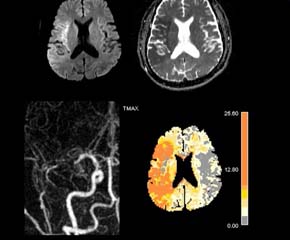

뇌경색 치료 방법

뇌경색 초기증상이 의심된다면 지금 바로 병원을 내방해 진단을 받고 적절한 치료를 손대는 것이 후유증을 감하는데 중요 해요. 시간이 관건이며, 뇌세포의 괴사, 증상 악화, 너무 늦으면 사망에 이를 수 있는 뇌혈관의 괴사를 피하기 위하여 증상이 나타난 뒤에 4시간 이내에 잘 맞은 약물, 시술 또는 수술을 신속히 실시해야 합니다. 치료로 즉시 하셔야 해요.